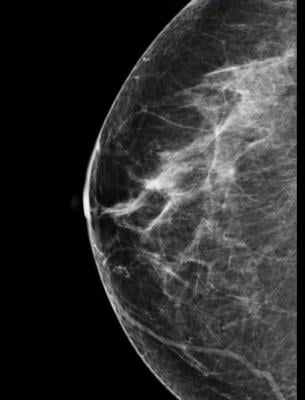

December 11, 2014 — The American College of Radiology (ACR) Mammography Case Review (MCR) Online improves physicians’ breast cancer detection skills by supplementing real world experience with electronic cases. This interactive eLearning program is a self-paced review that features a state-of-the-art interface with an interactive image detection mechanism to enhance learning.

The mobile compatible program offers image quality and a viewer control of brightness, contrast, zoom and pan of images. Expert feedback is integrated throughout the program, and scoring is provided by category. Real-time benchmarking allows learners to compare their performance to their peers.

· Focus on digital mammography, breast ultrasound, breast MRI, stereotactic and ultrasound-guided biopsy

· Demonstrate appropriate application of BI-RADS Atlas 5th edition descriptors and assessment categories for U.S. Food and Drug Administration regulations

· Distinguish normal and abnormal anatomic structures and breast lesions for biopsy